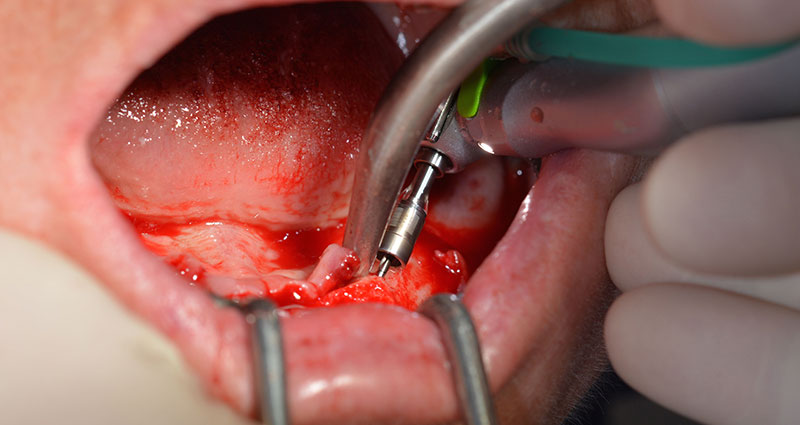

L’extraction de la denture résiduelle à la mandibule a exposé la crête alvéolaire de 37 à 47.

Le trou mentonnier doit d'abord être identifié comme une structure anatomique limitante, puis l'os cortical de la crête a été régularisé avec une pièce à main droite et une fraise sphérique de grande taille (Fig. 4).